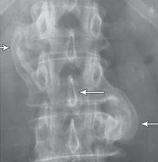

На рентгенограмме № 6 поясничного отдела позвоночника выраженный остеофитоз, спондилёз третьей степени, что также хорошо видно на МРТ № 39 поясничного отдела позвоночника МРТ № 40 ![]() МРТ № 41

На МРТ № 40 наблюдается типичный пример развития стеноза второго типа в шейном отделе позвоночника. И аналогичная картина, только, в поясничном отделе позвоночника, отображена на МРТ № 41 Стеноз Стеноз позвоночного канала встречается довольно часто, во всяком случае в моей практике. В данной книге я уже упоминал о том, что стеноз спинномозгового канала (то есть его сужение) может вызывать серьёзные осложнения при течении таких заболеваний, как например, грыжи межпозвонкового диска. Для лучшего понимания происходящих процессов давайте в общих чертах рассмотрим, что такое стеноз и чем он опасен. Итак, стеноз — это врождённое или приобретённое аномальное сужение просвета какого-либо полого органа (пищевода, кишечника, кровеносного сосуда и др.) или отверстия между полостями (например, при пороках сердца). Стеноз позвоночного канала характеризуется его патологическим сужением. Исходя из анатомо-физиологических особенностей позвоночного канала, который является вместилищем и в тоже время охранным футляром для спинного мозга, даже незначительное его сужение может оказаться фатальным для спинного мозга. К примеру, при развитии абсолютного стеноза позвоночника спинной мозг может быть компримирован (сжат) вместе с артериями. В свою очередь это неизбежно ведёт к развитию ишемии (от греч. ischo — «задерживаю, останавливаю» и haima — «кровь»; уменьшение кровоснабжения участка тела, органа или ткани вследствие ослабления или прекращения притока к нему артериальной крови) тех участков спинного мозга, где блокировано кровоснабжение сдавленными сосудами. Ещё в конце XIX века, а точнее в 1880 году, в своей работе М. Литтен отметил, что спинной мозг более чувствителен к ишемическим повреждениям и недостатку кислорода, чем другие ткани организма. А вот отечественному невропатологу, ученику В. М. Бехтерева и одному из первых нейрохирургов, Л. М. Пуссепу в 1902 году удалось в эксперименте на животных показать, что даже непродолжительная ишемия спинного мозга влечёт за собой некроз (отмирание) нервных клеток передних рогов спинного мозга. Если добавить к этому ещё и неизбежное нарушение ликвородинамики и развития (вследствие сдавления оболочек спинного мозга) эпидурита и арахноидита, то возникновение болевых, корешковых и сосудистых синдромов (в виде миелоишемии, радикулоишемии или миелорадикулоишемии) становятся вполне объяснимыми и понятными. Исходя из классификации, предложенной доктором I. Stephen, которой пользуется большинство авторов в своих работах, стеноз позвоночного канала позвоночника, как я уже упоминал, бывает двух типов. Тип первый — врождённый, или как его ещё называют идиопатический, то есть беспричинный (неизвестного, неясного происхождения). Второй тип — приобретённый, возникший вследствие дегенеративно-дистрофических процессов в позвоночнике, посттравматический или обусловленный другими причинами, которые привели к стенозированию (сужению) позвоночного канала. Например, грыжа межпозвонкового диска даже центральной локализации, имеющая размер всего 6 мм в дорсальном направлении в поясничном отделе позвоночника с сагиттальным размером спинномозгового канала в 15 мм приводит к формированию абсолютного стеноза второго типа (приобретённого) и может вызвать серьёзные осложнения. А при стенозе первого типа (врождённого, см. МРТ № 43), к примеру с сагиттальным размером спинномозгового канала в поясничном отделе 12 мм, даже трёхмиллиметровая протрузия межпозвонкового диска может привести к развитию слабости в ногах, мышечной атрофии или, как описывал данные состояния Dejerine ещё в 1911 г., «перемежающейся хромоте спинальной природы». |